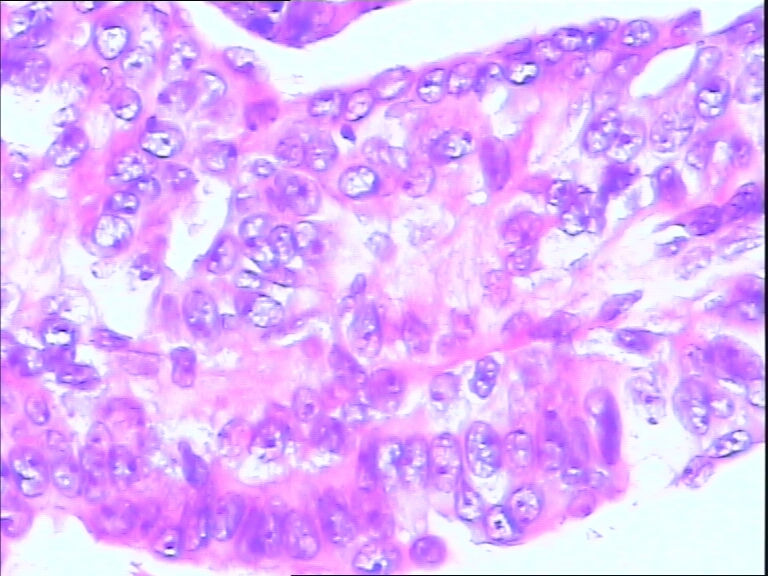

42y

左乳头有3mm结节

灰白不整形组织一块:0.7*0.5*0.4

导管内乳头状肿瘤